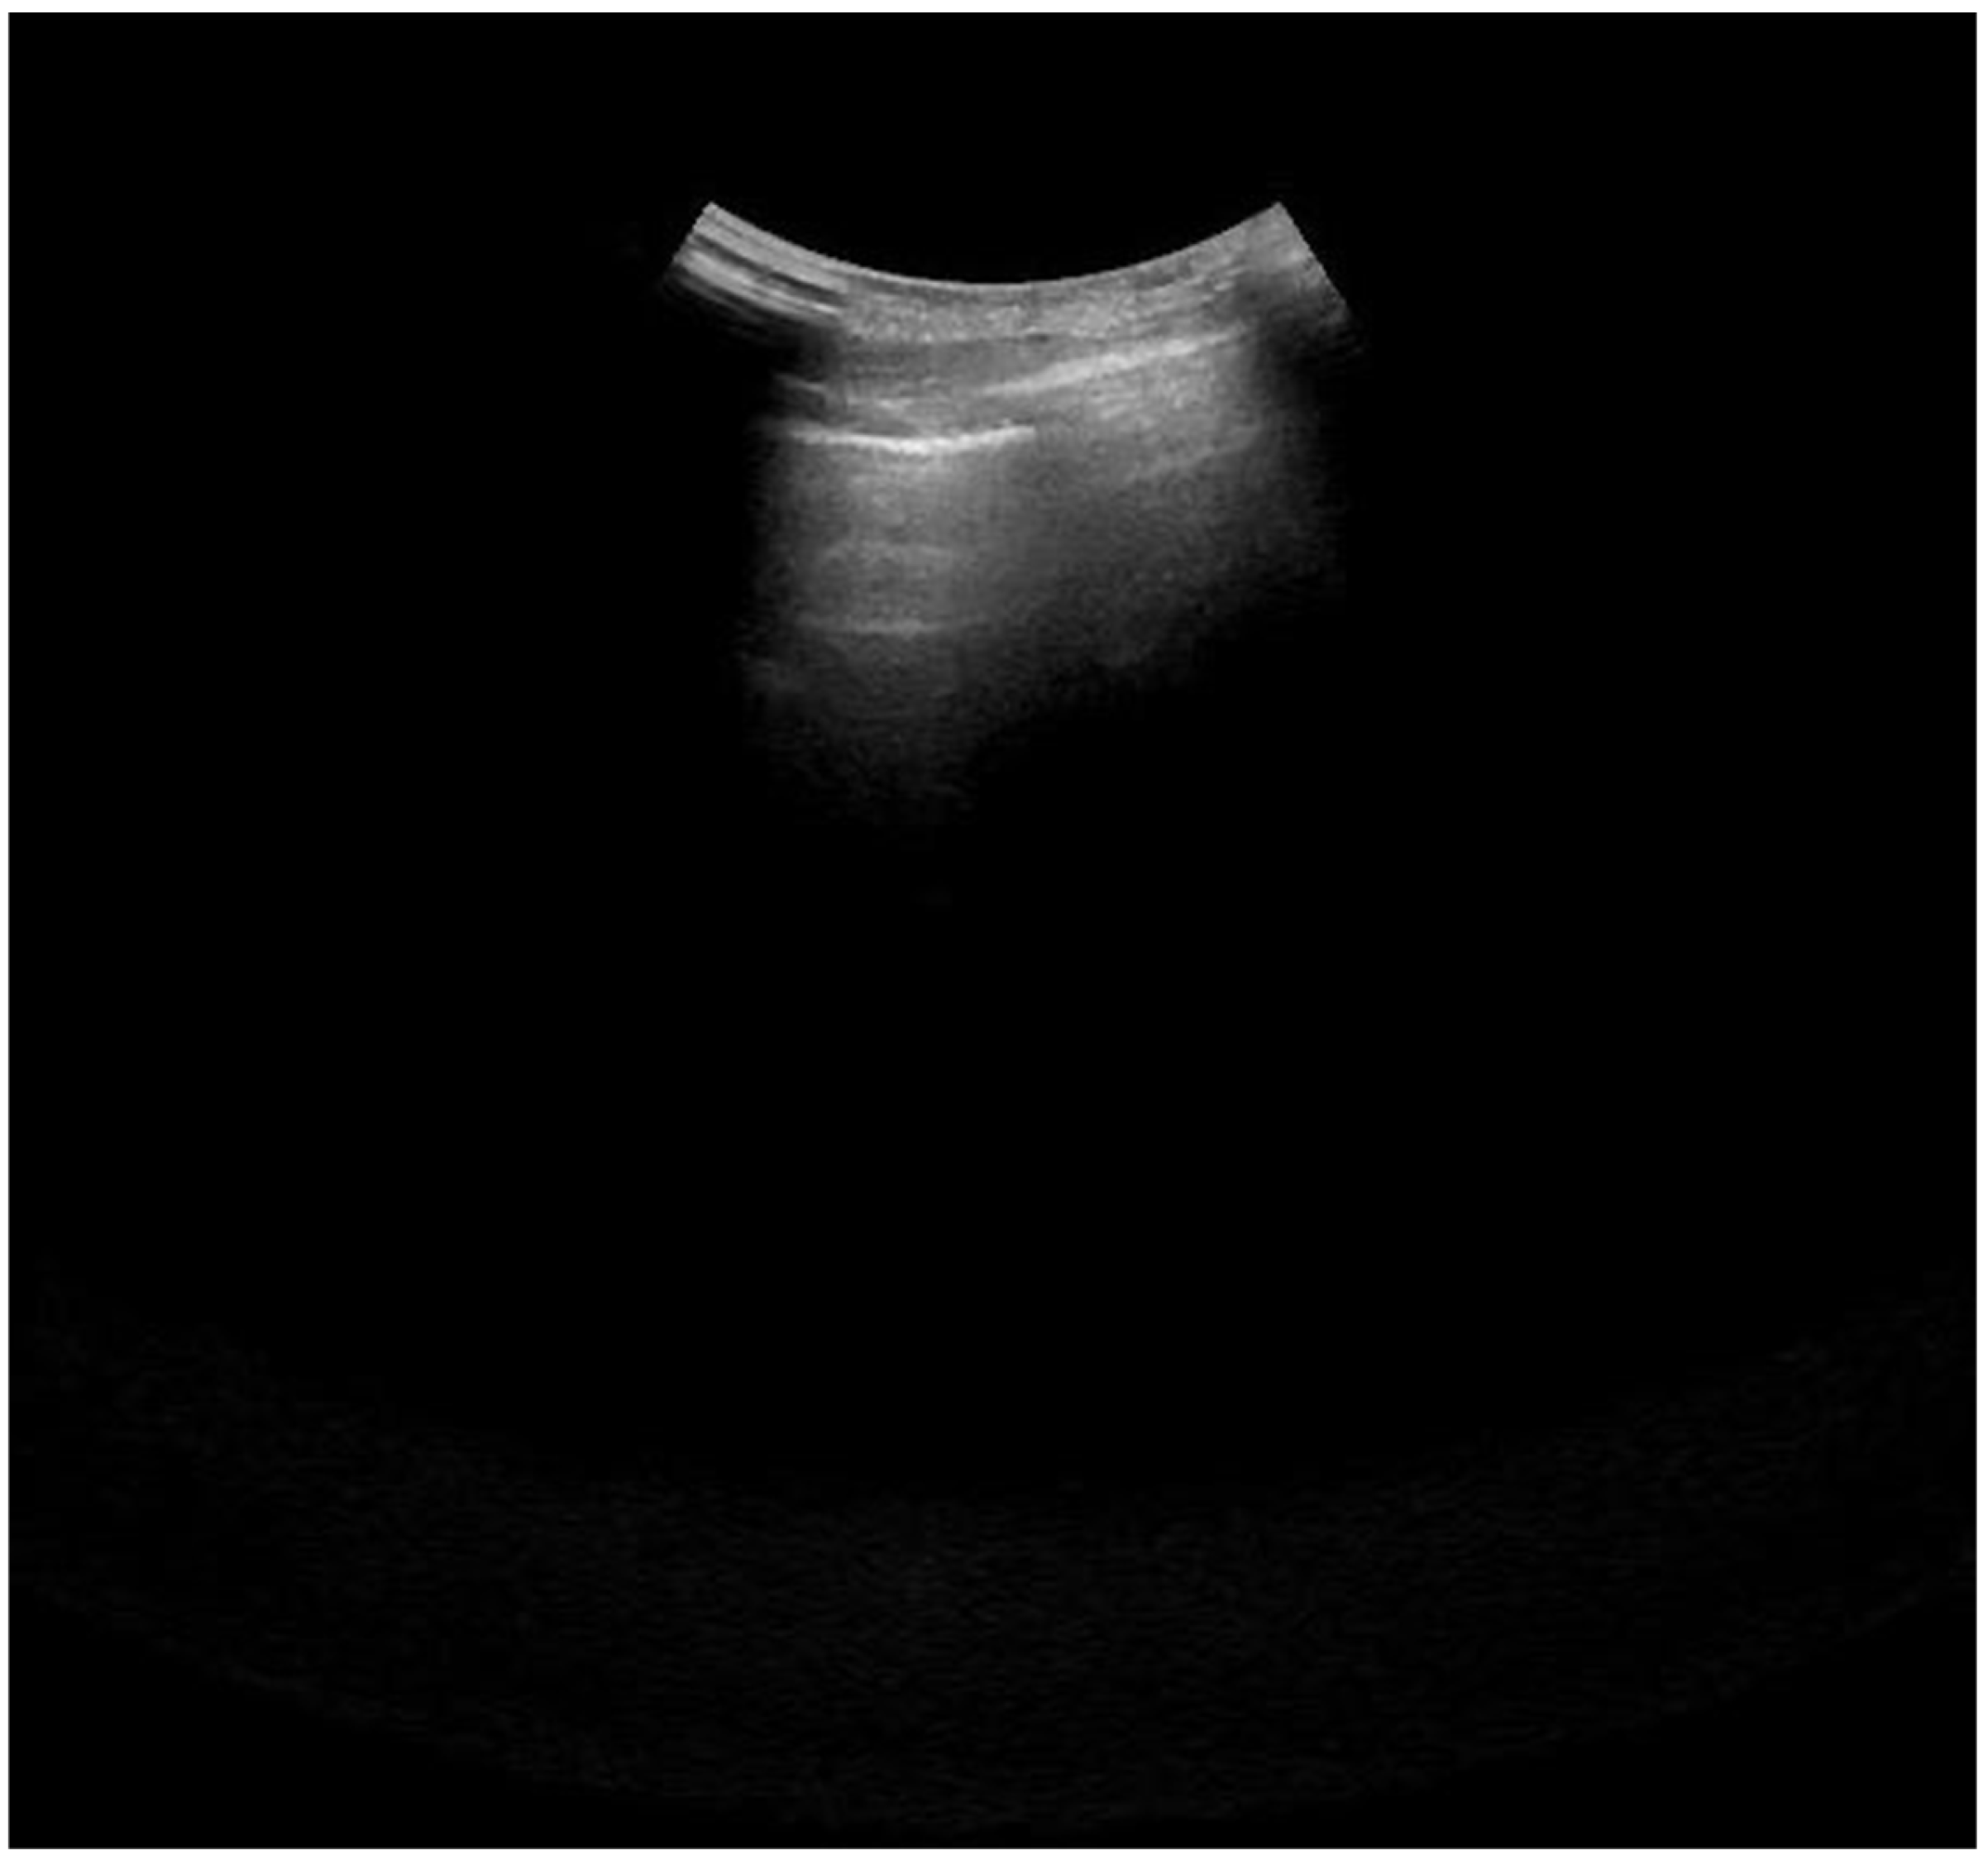

2.4. Lung Ultrasonography and Score Assessment

Appendix A